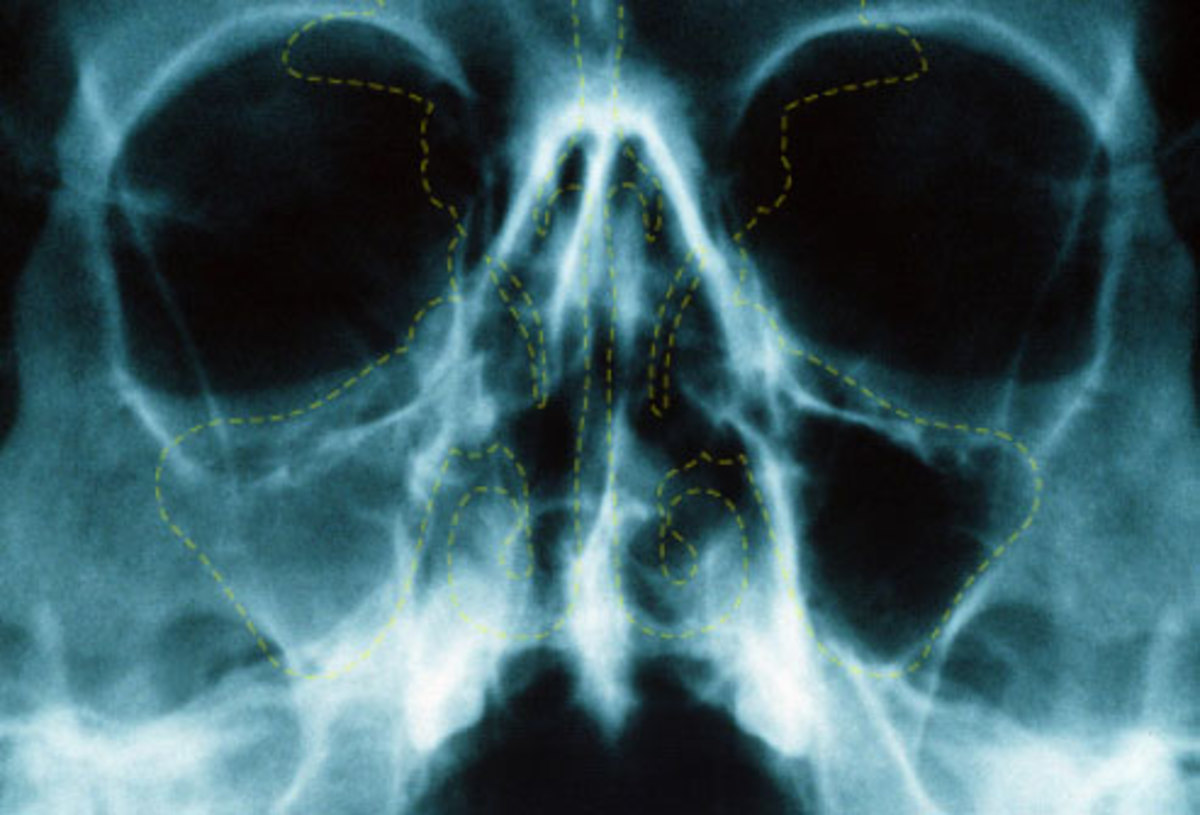

ΠΠ°Π½ΡΠΈΠ½ΡΡΠΈΡ — ΠΎΠ΄Π½Π° ΠΈΠ· ΡΠΎΡΠΌ ΠΎΡΡΡΠΎΠ³ΠΎ Π³Π½ΠΎΠΉΠ½ΠΎΠ³ΠΎ ΡΠΈΠ½ΡΡΠΈΡΠ°. ΠΡΠΈ ΠΏΠ°Π½ΡΠΈΠ½ΡΡΠΈΡΠ΅ Π²ΠΎΡΠΏΠ°Π»ΡΡΡΡΡ ΡΡΠ°Π·Ρ Π²ΡΠ΅ ΠΏΡΠΈΠ΄Π°ΡΠΎΡΠ½ΡΠ΅ ΠΏΠ°Π·ΡΡ ΠΈ ΡΠ΅ΡΠ΅ΠΏΠ°, ΡΡΠΎ ΡΠΎΠΏΡΠΎΠ²ΠΎΠΆΠ΄Π°Π΅ΡΡΡ Π½Π°ΠΊΠΎΠΏΠ»Π΅Π½ΠΈΠ΅ΠΌ Π² Π½ΠΈΡ Π±ΠΎΠ»ΡΡΠΎΠ³ΠΎ ΠΊΠΎΠ»ΠΈΡΠ΅ΡΡΠ²Π° Π³Π½ΠΎΡ ΠΈ ΡΠ»ΠΈΠ·ΠΈ. ΠΡΠΎ ΠΏΠ°ΡΠ½ΡΠ΅ (Π»Π΅Π²ΡΠ΅ ΠΈ ΠΏΡΠ°Π²ΡΠ΅) Π²Π΅ΡΡ Π½Π΅ΡΠ΅Π»ΡΡΡΠ½ΡΠ΅, ΠΊΠ»ΠΈΠ½ΠΎΠ²ΠΈΠ΄Π½ΡΠ΅, ΡΠ΅ΡΠ΅ΡΡΠ°ΡΡΠ΅ ΠΈ Π»ΠΎΠ±Π½ΡΠ΅ ΠΏΠ°Π·ΡΡ ΠΈ (Π ΠΈΡ 1.).

Π ΠΈΡ. 1. ΠΠ½Π°ΡΠΎΠΌΠΈΡ ΠΏΡΠΈΠ΄Π°ΡΠΎΡΠ½ΡΡ ΠΏΠ°Π·ΡΡ Π½ΠΎΡΠ°